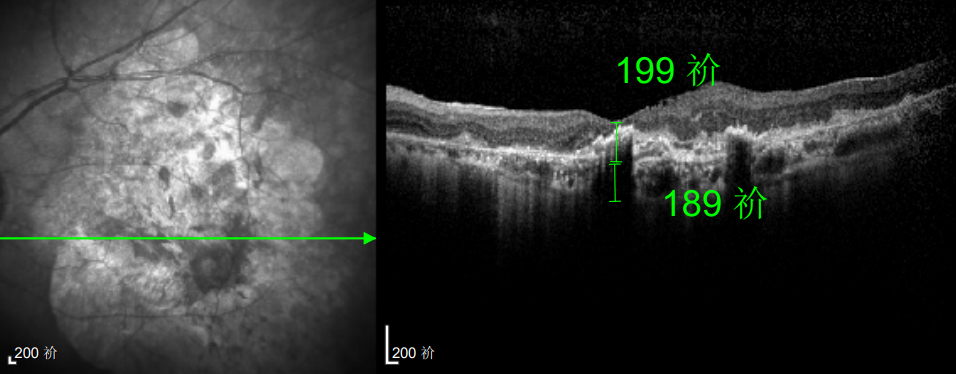

△延誤復查后的左眼

然而好景不長,半年后林婆婆的左眼視力突然驟降,甚至連眼前的人影都難以看清。但她仍抱有僥幸心理,覺得 “再打一針就能好”,恰逢春節(jié)臨近,便把復查的事一推再推,又延誤了3個多月才匆匆趕回醫(yī)院,可檢查結(jié)果卻給了她沉重一擊:由于病情延誤,持續(xù)的積液已造成黃斑的不可逆損壞,即便后續(xù)恢復治療,也難以回到理想水平。“當時真是腸子都悔青了!”回憶起這段經(jīng)歷,林婆婆至今仍難掩懊悔。